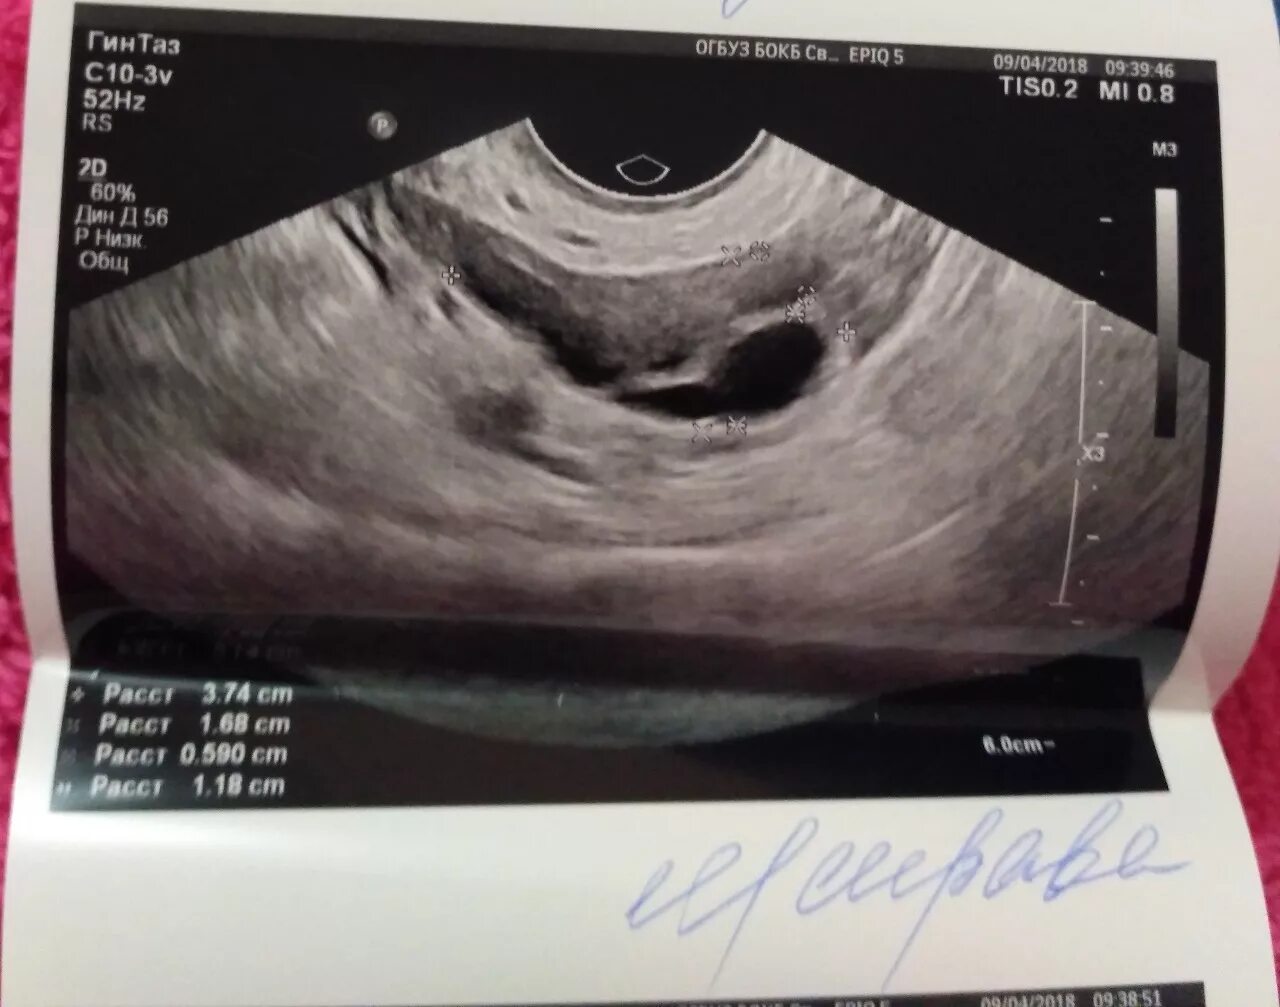

Цервикоз шейки матки